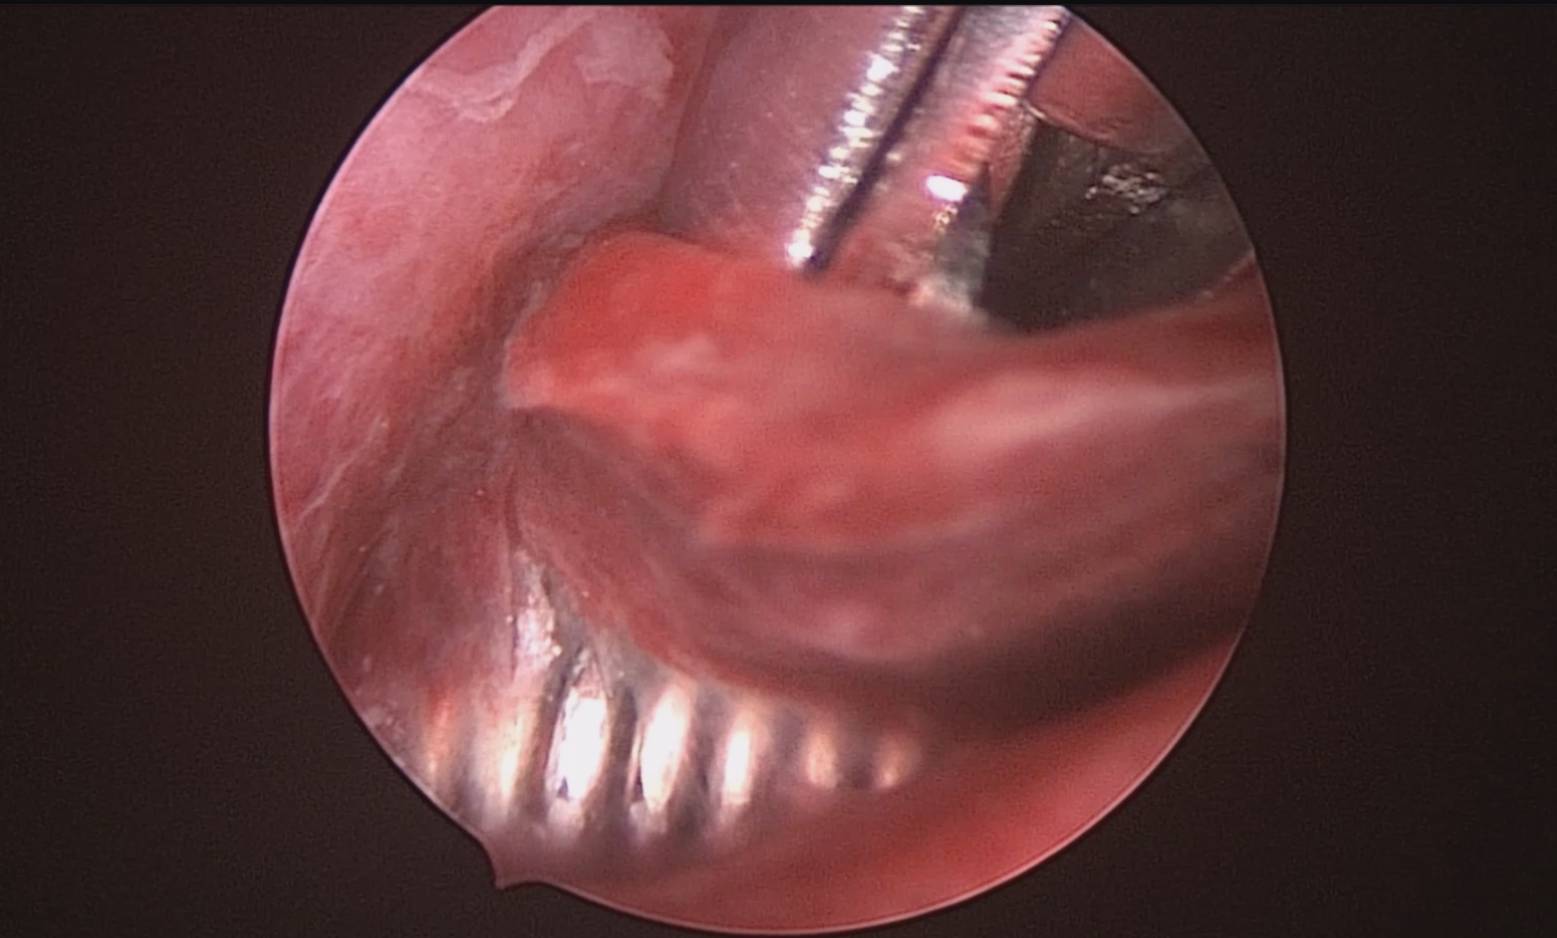

患者54岁,G2P1,顺产1次。安环26年,绝经1年,外院取环失败,子宫穿孔。宫腔镜术前B超提示子宫前位,盆腔未见异常。子宫极度前倾前屈位,宫腔下段后壁偏右穿孔,宫腔镜进入盆腔,见肠脂垂,未见积血,宫腔镜退出盆腔,寻找节育环。手术大部分时间在寻找宫颈内口和宫腔方向,在子宫穿孔的左上方找到宫颈内口,宫腔镜艰难进入宫腔,异物钳取环就迎刃而解了,取出一枚O型环。